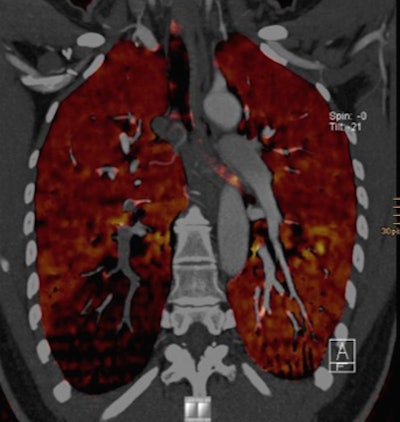

| Above, CTA showing an axial scan with an embolus at the right lower lobe. Below, corresponding coronal pulmonary blood volume map shows a perfusion defect of the right lower lobe. Images courtesy of Tobias de Zordo, MD, and Gudrun Feuchtner, MD. |

On DSCT images, seven patients with pulmonary emboli showed perfusion defects in the corresponding lung parenchyma. In one patient, a triangular perfusion defect was found without a corresponding pulmonary embolus. "We didn't have any additional perfusion defects; we don't know if it's artifact or something else -- the lung window couldn't find anything," he said.

High-pitch dual-source CT allows for significantly reduced radiation exposure, while providing complementary evaluation of perfusion defects, de Zordo concluded.